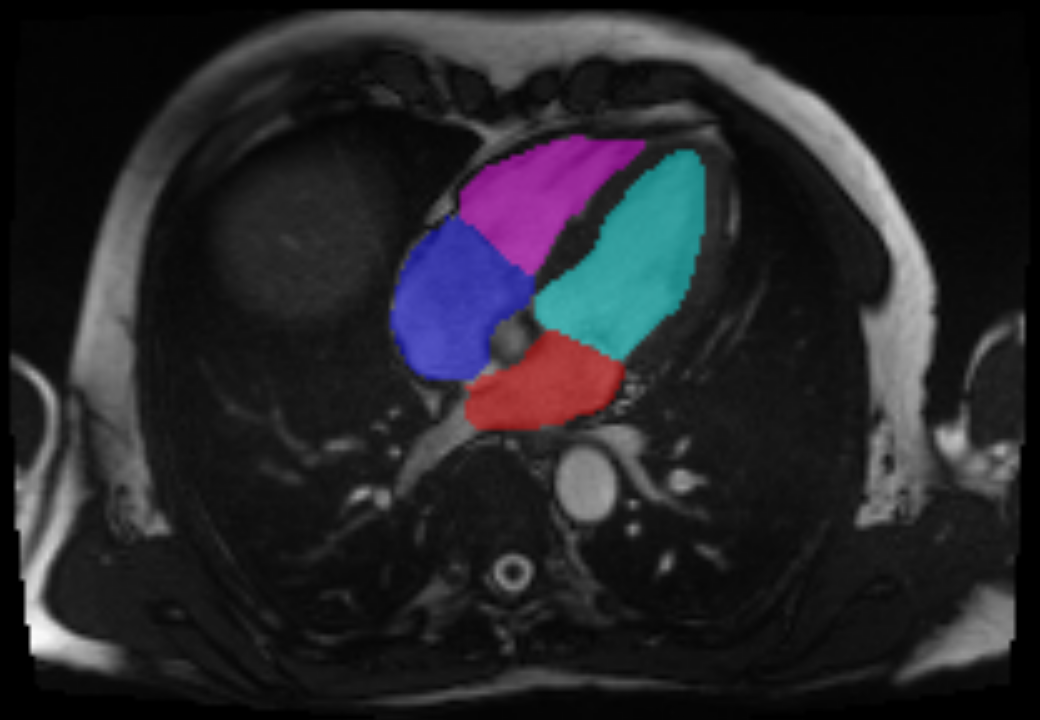

The CMR imaging data from the UK Biobank that is relevant to MR detection includes long-axis 2-chamber (2CH) view and long-axis 4-chamber (4CH) view, which are all shown in Figure 2. In addition, the short-axis view CMR provides accurate description of the left ventricle. Both long-axis views and short-axis view are used to estimate heart measurements relevant to the MR detection task, while only the long-axis 4CH view is used for the deep learning models.

As a pre-processing step, we performed semantic segmentation on the CMR imaging data, using masks (Figure 2) generated by a U-Net [18] segmentation model to highlight regions of interest to MR classification. U-Net is currently the leading model architecture for medical imaging segmentation, with various U-Net variants developed for different applications. TernausNet [12] is a U-Net variant that reshapes the U-Net encoder to match the VGG11 architecture, allowing it to use pre-trained VGG11 [19] model weights for faster convergence and improved segmentation results. While most medical imaging segmentation models are trained using supervised learning, weakly supervised segmentation methods such as VoxelMorph augmented segmentation [27], ACNN [16], CCNN [13], graph-based unsupervised segmentation [15], and GAN-based unsupervised segmentation [23, 24] also produce comparable segmentation results. For the segmentation of the 4CH, 2CH, SA, and aorta view CMR imaging dataset from the UK Biobank, Bai et al. [2] offer a supervised segmentation model.

Figure 2: Example of the segmentation outputs of the long axis 4CH (left), 2CH (middle) CMR view imaging data and the short axis (right) CMR imaging data.

We manually labeled 100 CMR images for each view and trained a supervised segmentation model with the TernausNet [12] architecture. Then, segmentation outputs, shown in Figure 2, are used to compute measurements of cardiac structure and function for the four chambers of the heart, as summarized in Table 1. The short-axis view CMR segmentation output is used to estimate the left ventricle and right ventricle measurements, while the long-axis 4CH view and 2CH view outputs are used to estimate the left atrium and right atrium measurements. Specifically, the left atrial volume is estimated using the biplane method with segmentation of both the 2CH and 4CH view, while the right atrial volume is estimated using single plane method with segmentation of the 4CH view.